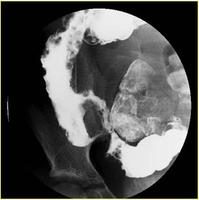

x线检查[编辑 | 编辑源代码]

肠道钡餐造影能了解末端回肠或其他小肠的病变和范围。其表现有胃肠道的炎性病变,如裂隙状溃疡、卵石征、假息肉、单发或多发性狭窄、痰管形成等,病变呈节段性分布。钡剂灌肠有助于结肠病变的诊断,气钡双重造影可提高诊断率。X线腹部平片可见肠拌扩张和肠外块影。腹部CT,检查对确定是否有增厚且相互分隔的肠袢,而且与腹腔内脓肿进行鉴别诊断有一定价值。